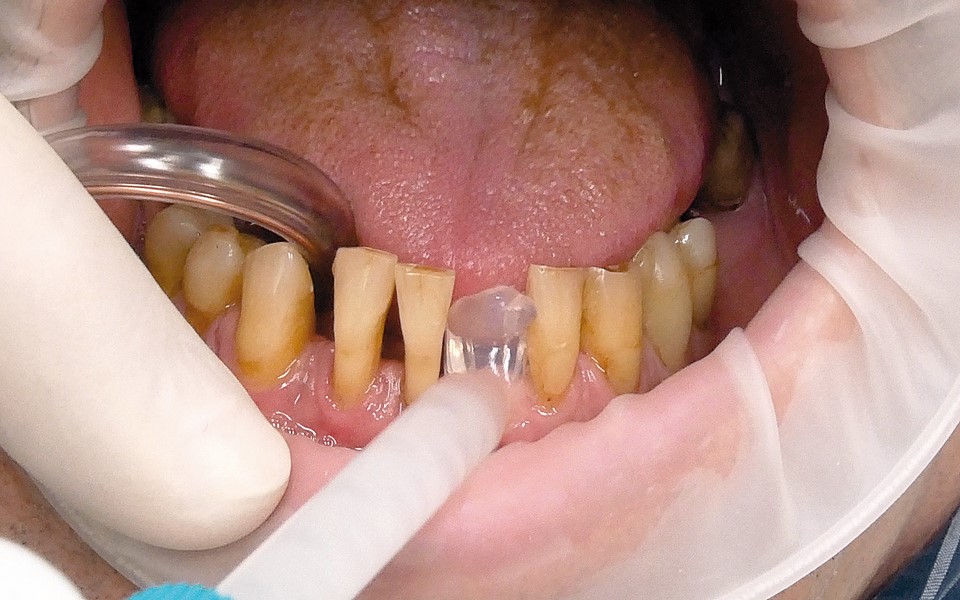

Jedną z popularniejszych metod stabilizacji zębów rozchwianych jest ich szynowanie. Metoda ta, wspierająca inne metody leczenia, jest powszechnie stosowana. Jednym z najnowocześniejszych materiałów wykorzystywanych w stomatologii do szynowania zębów jest taśma poliaramidowa. W opisanym przypadku autorzy pracy przedstawiają sposób uproszczenia całej procedury i ograniczenia ryzyka popełnienia błędu, szczególnie w sytuacji całkowitej utraty zęba. Uzyskano to dzięki zastosowaniu indeksu wykonanego z przezroczystego silikonu.

One of the more popular methods of stabilising loose teeth is to splint them. This method, aiding other methods of treatment, is generally used. One of the most modern materials used in dentistry for splinting teeth, is polyamide tape. In the case described the authors show how to simplify the whole procedure and limit the risk of making a mistake, particularly in the situation of total loss of one tooth. This was achieved thanks to the use of an index made out of transparent silicone.